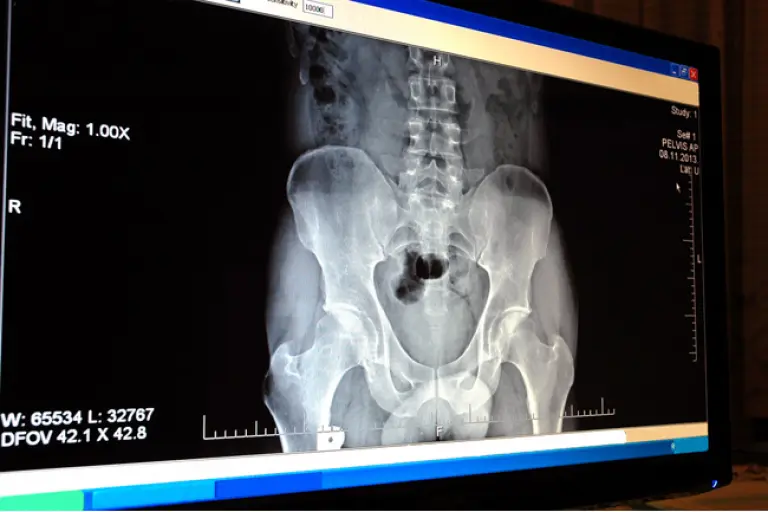

El sistema ARiX RAD sustituye la película radiográfica por un detector de radiación, el cual provee? señales ?eléctricas ?para generar una imagen digital.

Con el objetivo de sustituir los aparatos médicos que toman rayos X, la Compañía Mexicana de Radiología (CMR) creó un sistema de adquisición digital de imágenes radiográficas, que sustituye la placa tradicional por un detector de estado sólido, el cual entrega resultados en cinco segundos. Los equipos analógicos tardan seis minutos en el revelado.

La ingeniera Nashelli Cuaranta Monroy, investigadora del CMR, explicó que el llamado sistema ARiX RAD obtiene imágenes de rayos X que sirven de apoyo en el diagnóstico de diferentes patologías, como lo es identificar fracturas óseas, cálculos renales o tumores.

Esta imagen digital permite realizar una valoración más acertada mediante el uso de herramientas de software que habilitan el realce y posproceso de la radiografía que se despliega en monitores convencionales. Además, el control y manejo virtual facilita su distribución por medio de Internet, habilitando procesos como la telerradiología o el diagnóstico remoto.

El sistema permite realizar mediciones especializadas en forma automática como el índice cardiotorácico (determina crecimiento anormal del corazón), ángulo de Cobb (detecta escoliosis lumbar), aplicación de filtros que resaltan estructuras diferentes como el tejido blando y huesos.